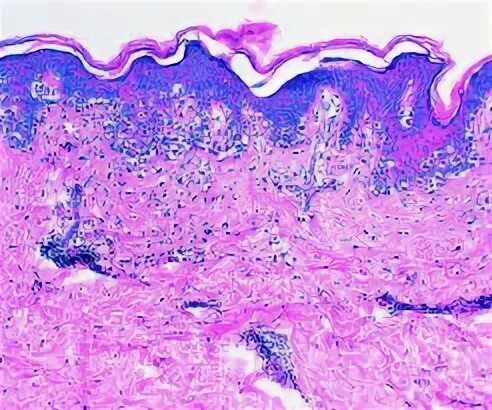

Солнечный эластоз